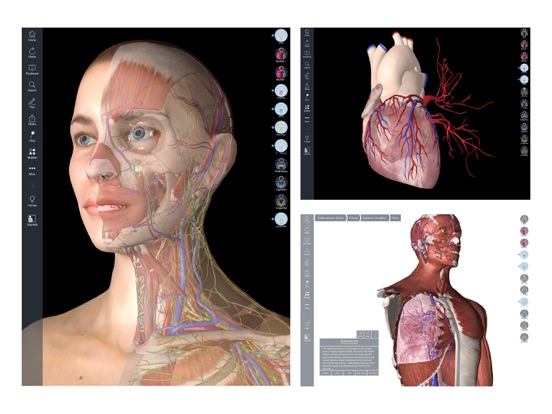

Downloading Essential Anatomy 5 IPA for iOS is a convenient and useful way to explore the world of human anatomy right from the comfort of your iPhone or iPad. This app provides a comprehensive and detailed view of the human body, allowing users to interact with various systems and structures. With stunning 3D graphics, it offers a visually captivating experience that aids in understanding and learning about the complexities of the human body. Whether you are a medical student, healthcare professional, or someone with a general interest in anatomy, Essential Anatomy 5 IPA is a must-have app that provides a wealth of knowledge at your fingertips. The app’s intuitive interface and easy navigation make it accessible to users of all levels of expertise. With just a few taps, you can delve into different layers of the body, explore various organs, muscles, and bones, and gain a deeper understanding of human anatomy. Download Essential Anatomy 5 IPA today and elevate your knowledge and appreciation of the human body.

The Essential Anatomy 5 IPA for iPhone is an incredible tool for medical students, professionals, and anyone interested in learning more about the human body. This app provides a comprehensive and detailed 3D model of the human anatomy, allowing users to explore and study different parts of the body with ease. With its user-friendly interface and interactive features, users can zoom in, rotate, and examine every angle of the human body, from bones and muscles to organs and systems. The app also provides in-depth information about each structure, making it a valuable resource for studying and understanding the intricacies of human anatomy. Whether you’re a medical student preparing for exams or simply curious about the wonders of the human body, the Essential Anatomy 5 IPA for iPhone is an essential tool to have at your fingertips.

Essential Anatomy 5 IPA MOD IOS is a revolutionary app that has changed the way we learn about the human body. With its advanced features and stunning visuals, this app provides an immersive and interactive experience for users. Whether you are a medical student, healthcare professional, or simply interested in learning about anatomy, Essential Anatomy 5 is a must-have tool. It offers a comprehensive library of detailed 3D models, allowing users to explore every aspect of the human body. From the skeletal system to the muscular system, nervous system to cardiovascular system, this app covers it all. Additionally, it provides in-depth information on each structure, including names, functions, and clinical relevance. With its user-friendly interface and intuitive controls, navigating through the app is a breeze. Overall, Essential Anatomy 5 IPA MOD IOS is an essential resource that brings anatomy to life, making it an invaluable tool for anyone interested in the human body.

This app provides a comprehensive and detailed 3D representation of the human body. With over 8,200 anatomical structures, including muscles, bones, organs, and more, it offers a level of accuracy and depth that is unparalleled. Whether you are studying for an exam or explaining a medical condition to a patient, Essential Anatomy 5 IPA has the information you need.

Essential Anatomy 5 IPA allows users to interact with the 3D models, zooming in and rotating them to explore every angle. The user-friendly interface makes navigating through the app a breeze, and the intuitive controls ensure that anyone, regardless of their level of expertise, can easily explore and understand the complex anatomical structures.

One of the standout features of Essential Anatomy 5 IPA is its ability to showcase cross-sectional views of the body. This enables users to see the internal structures and their relationships with each other, providing a deeper understanding of the body’s intricate systems. This feature is particularly useful for students learning about the different body cavities or professionals wanting to explain surgical procedures to their patients.